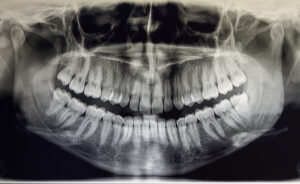

X-Rays and Radiation Safety Principles in Dentistry

Dental x-rays are important for maintaining an individual’s optimal oral health. Like with any x-ray procedure, there are radiation safety principles that have been put in place to protect both